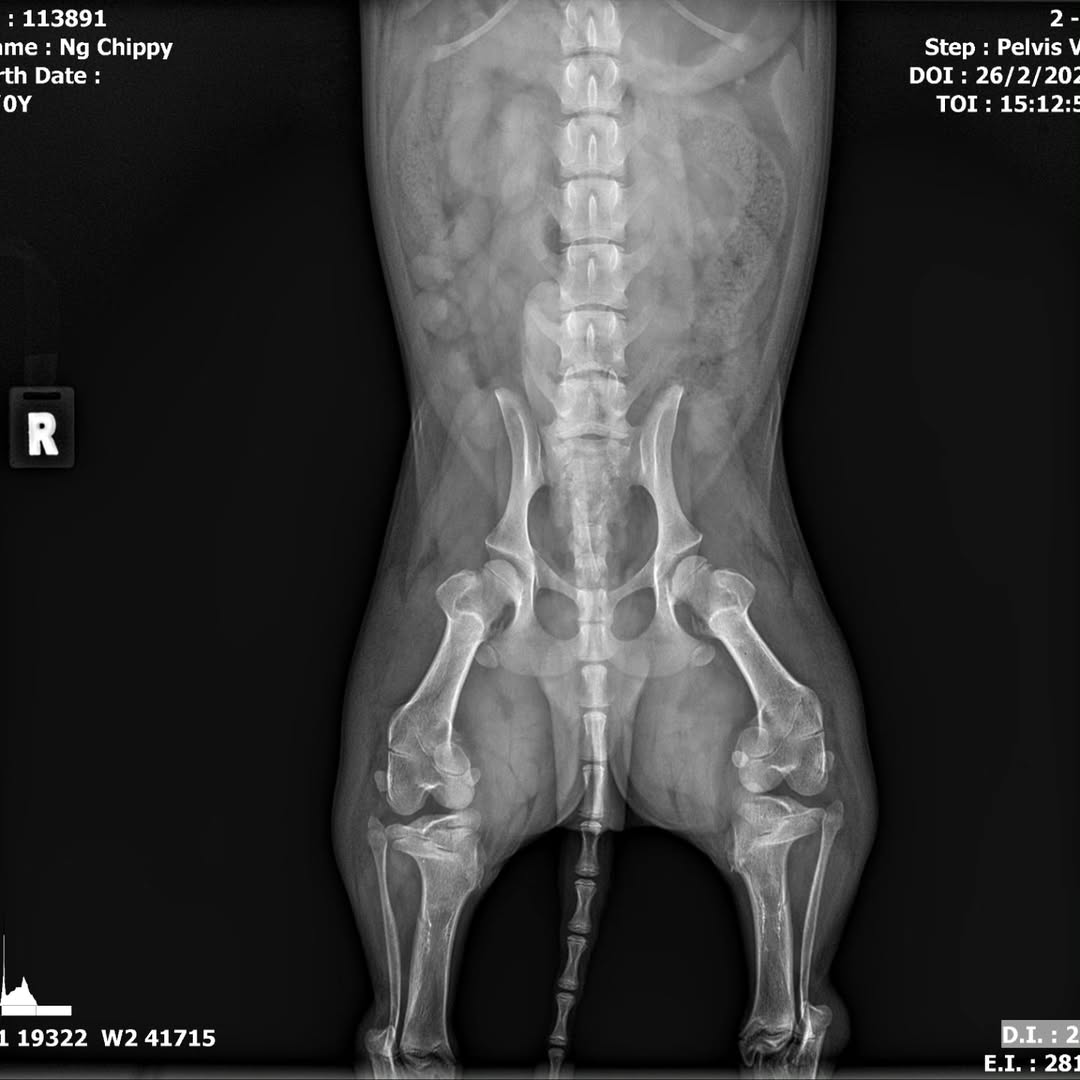

Meanwhile, Chippy suffers from severe torsional deformity. The rescuer says she is awaiting his CT scan results to know his exact condition.

Meanwhile, Chippy will need separate surgeries for his legs.

“While Chippy is not in pain like Daley, his condition is complicated and worse than Daley in some ways,” the rescuer explained in an Instagram post. “Only after CT scan will he be able to tell us how extensive the surgery for Chippy will be.”

“For Chippy, we had a rough estimation of S$12,000 each leg, so S$24,000,” she added.

An X-ray of Chippy’s legs. Source: @chippy.daley.dcorgis on Instagram